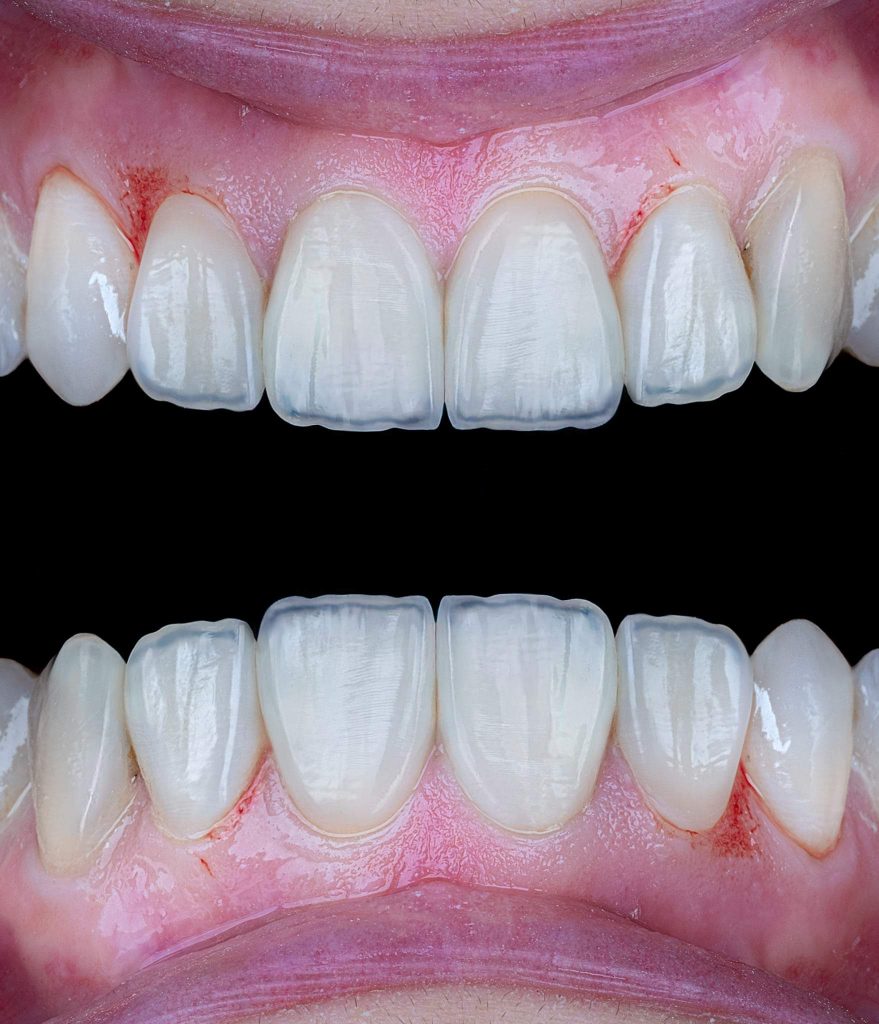

3. Step-by-step clinical procedure

The clinical treatment steps are presented in the images below, with a simple description below each image.

Clinical note: In this case, the wax-up was made only for the central and lateral incisors. However, during the clinical procedure, I noticed that the canines were also needed some correction by composite materials to achieve better morphological shapes, and to provide better smile curve.